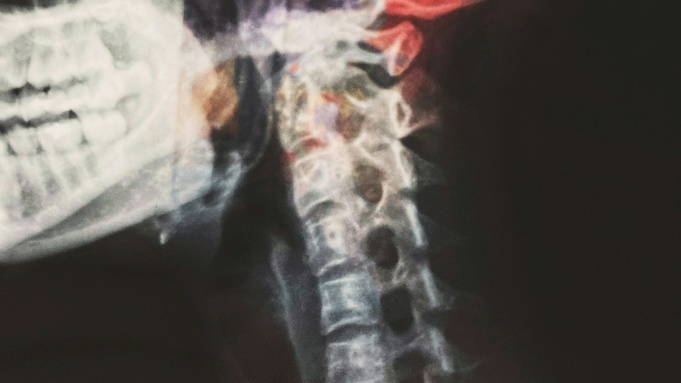

В Павловском районе школьница получила травмы головы, шеи и позвоночника, играя со сверстниками в "цепи кованые" в оздоровительном лагере. Алтайская прокуратура добилась взыскания компенсации морального вреда со школы, на территории которой это произошло, сообщили в пресс-службе ведомства.

"Летом 2023 года несовершеннолетняя, находясь в оздоровительном лагере при МБОУ "Комсомольская СОШ № 1", участвовала в игре "цепи кованые", в ходе которой упала, ударившись головой и спиной о тротуарную плитку. В результате падения девочка получила травму головы, шеи и позвоночника", – говорится в сообщении.